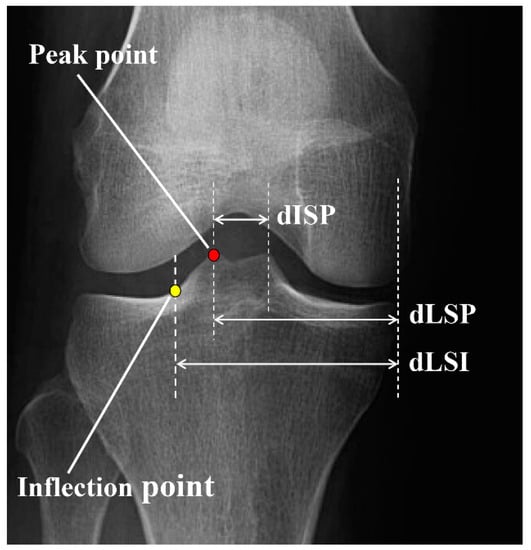

The peak and inflection points of the lateral tibial spine were determined as the most prominent points and the intersection point between the tibial spine slope and the tibial plateau, respectively. The distance between the medial tibial border and lateral spine peak point (dLSP), the distance between the medial tibial border and lateral spine inflection point (dLSI), and the mediolateral inter-spine distance (dISP) were measured and presented as a percentage of the entire tibial plateau width (Figure 1).

Figure 1. Radiographic measurements of the lateral tibial spine. Peak point: the most prominent point of the lateral tibial spine, inflection point: the intersection point between the tibial spine slope and tibial plateau, dLSP: distance between the tibial medial border and lateral spine peak point, dLSI: distance between the tibial medial border and lateral spine inflection point; dISP: medio-lateral inter-spine distance.